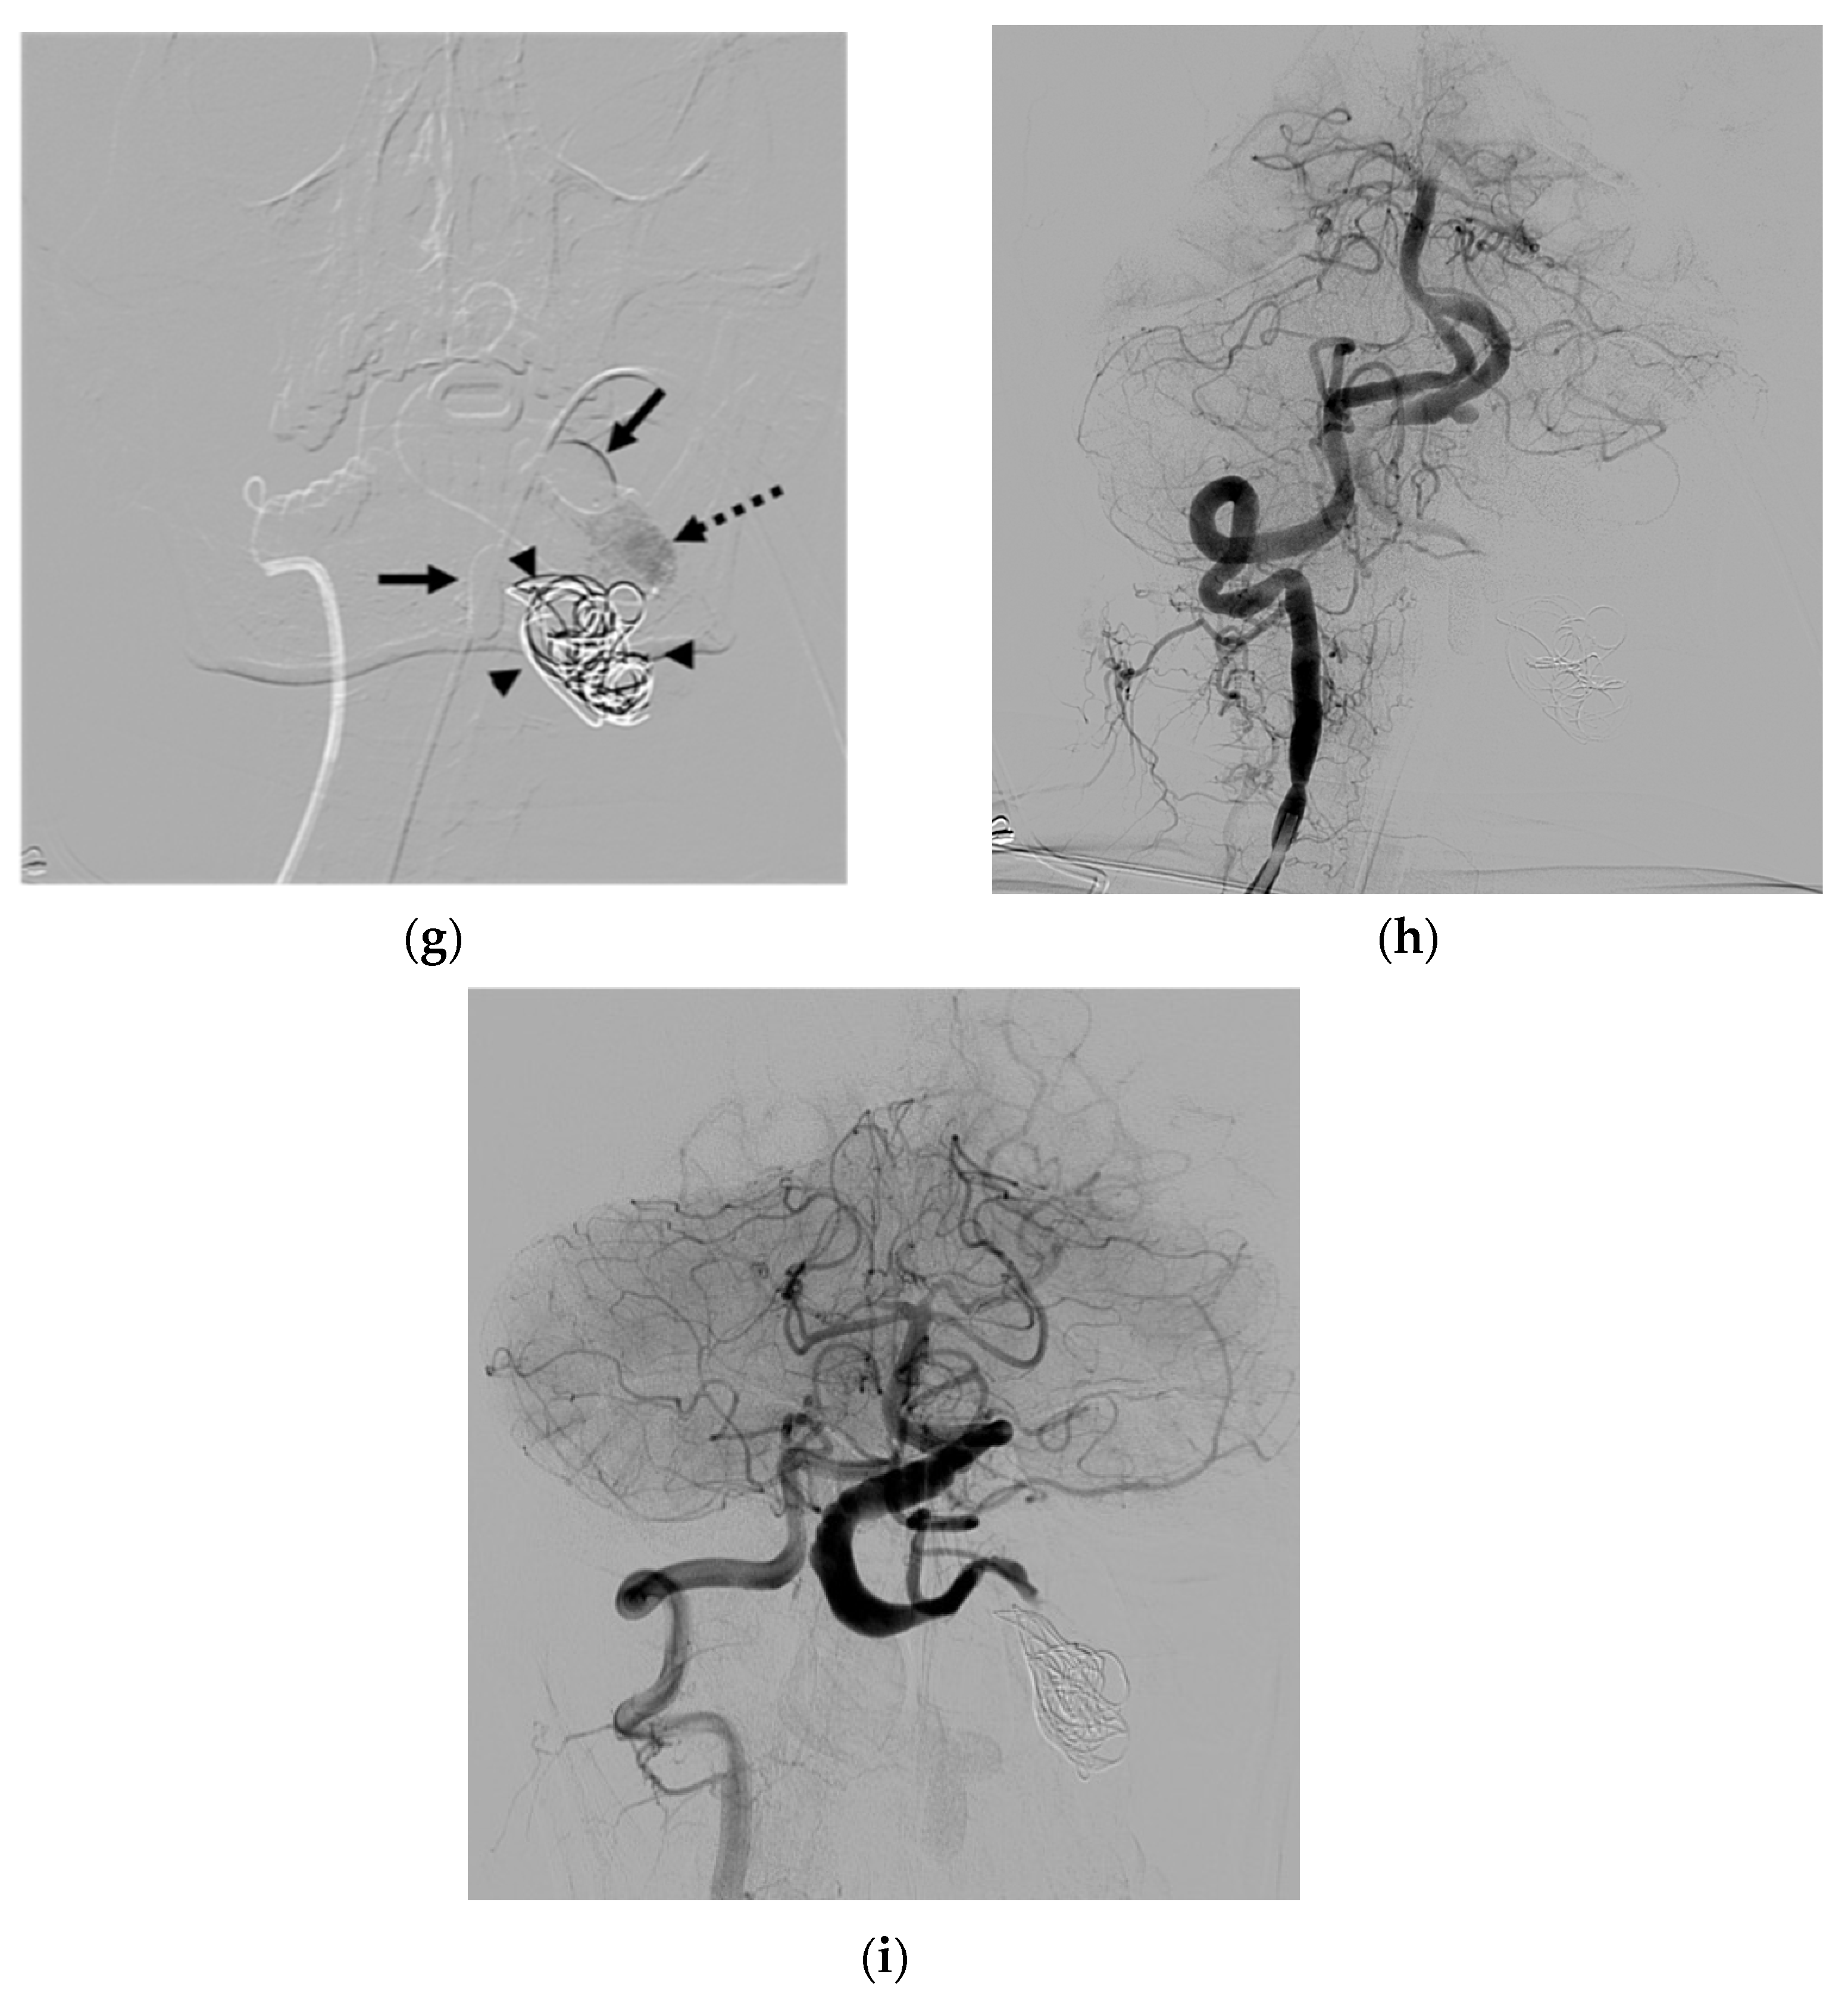

| 2 | F | 33 | Bleeding | Central line injury | T | VVP | N | C | O | Improved | None |

| 3 | F | 79 | Congestive heart failure | Unknown | S | IJV; subclavian vein | N | C | P | Improved | Puncture-site hematoma |

| 4 | F | 62 | Tinnitus | Unknown | S | VVP | N | B | O | Improved | Transient occipital pain |

| 5 | F | 50 | Right arm weakness | Unknown | S | Radicular vein; peri- medullary veins | N | B and C | O | Improved | None |